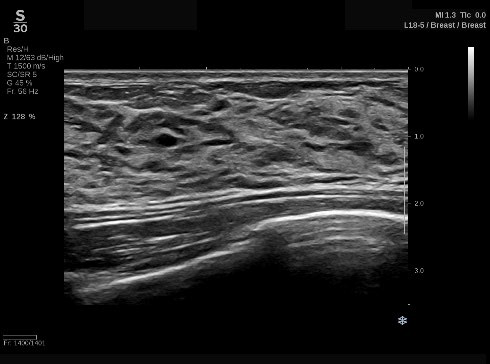

(1)独自のUltraFastTM テクノロジーにより高画質な画像を実現

パワフルなプロセッサを搭載し、データを高速演算処理するUltraFastTMImaging 技術を駆使することにより、最大20,000 フレーム/秒※1 の処理速度で高速に画像を構築する。